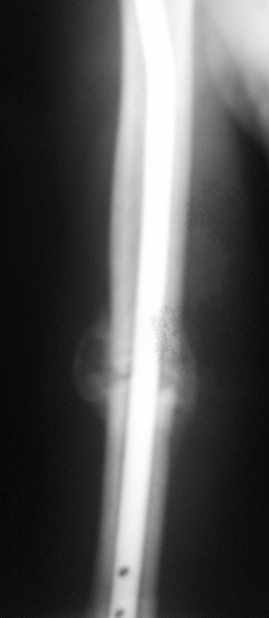

Блокируемый незаблокированный штифт.

однозначно не блокировать и не убирать - есть прекрасная мозоль и все отлично срастается. Мне плохо видно - выступает ли гвоздь проксимально ( кажется, нет, гвоздь строго в уровень с костью)?

Спасибо. А не слишком ли хороша мозоль?

Большая мозоль - здоровый организм УСПЕШНО компенсирует недостатки фиксации.

Раз есть боль в области плеча - скорее всего, таки травмируется ротаторная манжета плеча гвоздем - либо подождать еще месяцок и гвоздь убрать, пока он больному не разорвал манжету "в клочья", либо (в идеале, если есть желание, операционное время, инструмент того же производителя, которым пользовались в Склифе, понимание со стороны больного и т.д) - забить гвоздь на полсантиметра глубже и заблокировать одним проксимальным шурупом, чтоб предотвратить его миграцию в канале

Само же состояние перелома мне не внушает никаких сомнений или опасений

Гвоздь для плеча - дело не очень хорошее, и, честно говоря, на этих снимках показаний к такому методу лечения я никаких не вижу. Больше процент несращений, часто (до 20-30 процентов) встречаются осложнения со стороны плечевого сустава... Однако, это уже выходит за пределы обсуждаемой темы

Пациент обратился с жалобой на лигатурный свищ.

Амплитуда движений 70-80% от контрлаптеральной конечности с умеренной болью в месте перелома. Наиболее болезненно - заведение руки за спину (появляется боль в области плечевого сустава). Отведение - градусов 70, далее за счет лопатки.

Обычное дело, пусть разрабатывает давно, лучше с методистом. Тут по снимкам проблем не видно. Винты вводить необязательно - если хирург знает, что делает. Например, если получился хороший press-fit из-за несоответствия формы гвоздя и канала.